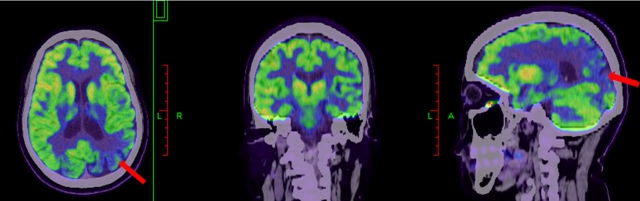

利用脑部影像学技术,如MRI可以发现特异区域的萎缩;PET-CT扫描,可以检测大脑中的异常蛋白质堆积或其他结构变化(见下图)。

阿尔茨海默病患者FDG-PET,可显示颞顶叶葡萄糖代谢减低(红色箭头所示)